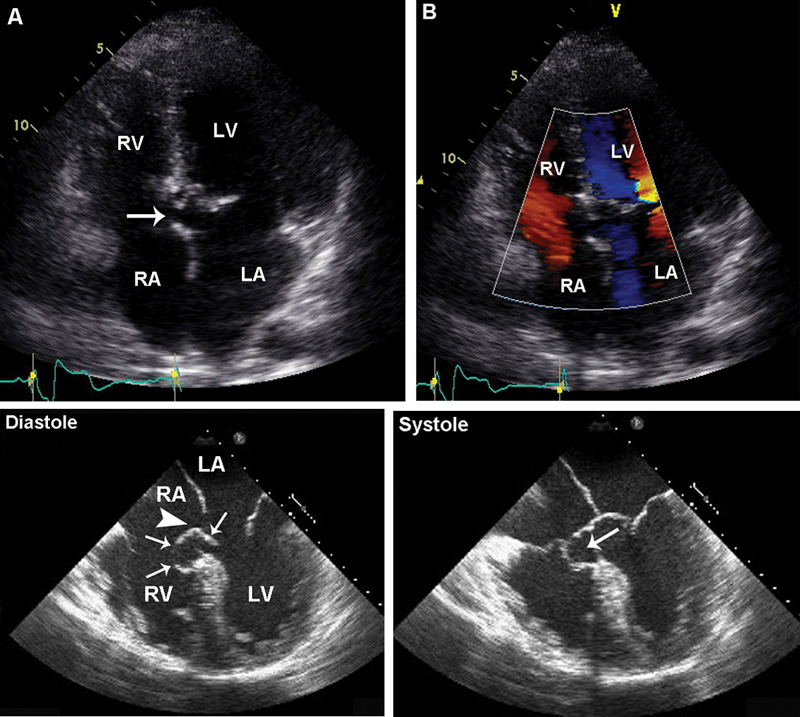

فحوصات تشخيصية لبعض امراض القلب والشرايين التاجية